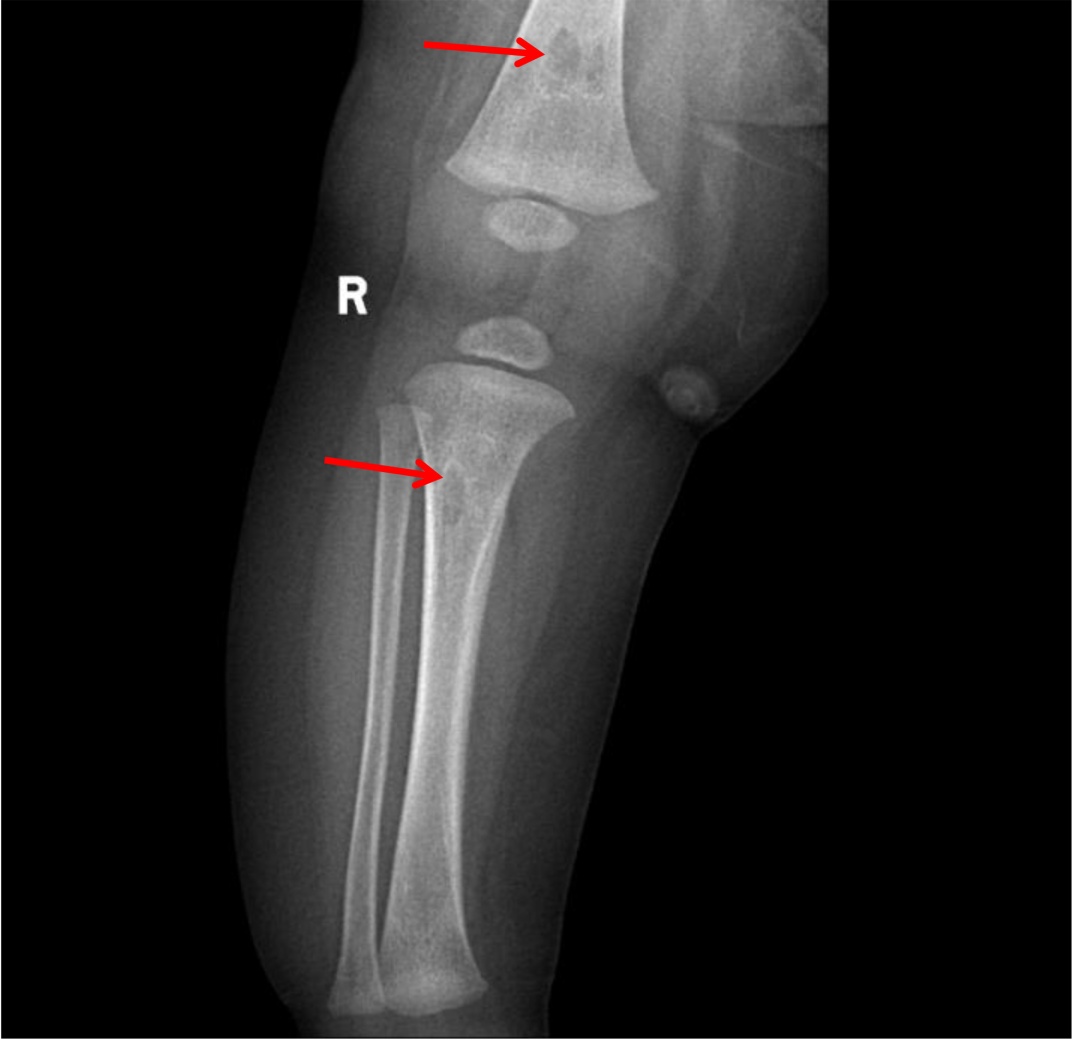

(4) 辅助检查:2025-09-07胸部X线:考虑双肺少许炎症;2025-09-08尿培养:铜绿假单胞菌,头孢他啶2S;2025-09-09血常规 + CRP复查:C反应蛋白30.88 (mg/L)↑,白细胞计数7.63 (×10^9/L) ,中性粒细胞百分率35.10↓,淋巴细胞百分比52.30%↑,淋巴细胞绝对值3.99 (×10^9/L)↑,血红蛋白88 (g/L)↓,血小板计数407 (×10^9/L)↑,血沉49.00↑,白介素644.55 pg/mL:2025-09-09免疫全套:免疫球蛋白IgG 3.48 g/L↓,免疫球蛋白IgGM 0.50 g/L,免疫球蛋白IgA 0.05 g/L↓,补体C3 1.69 g/L↑,补体C4 0.33 g/L;碱性磷酸酶:305.3U/L↑;2025-09-09左侧髋关节及左侧膝关节彩超:未见明显异常;2025-09-09胫腓骨正侧位X线(如图1):左腓骨形态略膨隆,髓腔内见长节段低密度区,边界不清,骨皮质膨胀、变薄,层状骨膜反应,邻近软组织肿胀。

Figure 1. Left tibia fibula AP & LAT X-ray

1. 左侧胫腓骨正侧位片

左腓骨形态略膨隆,髓腔内见长节段低密度区,边界不清,骨皮质膨胀、变薄,层状骨膜反应,邻近软组织肿胀。